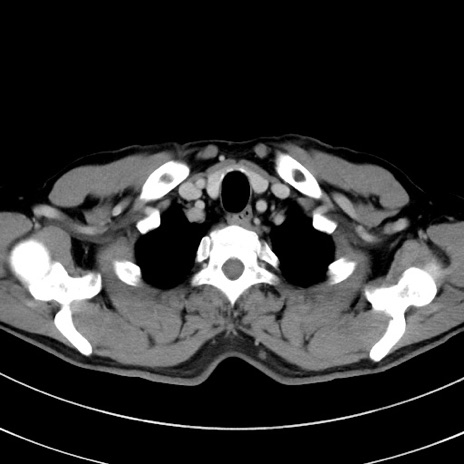

症例8(横断像)

【症例】 60歳代男性

【主訴】 黒色吐物

【現病歴】 4日前から嘔気自覚、2日前の朝食後にも嘔気あり、自分で手で嘔吐反射起こし嘔吐したところ血が混ざっていたため受診。

【既往歴】 5年前汎発性腹膜炎を伴う急性虫垂炎で手術、高血圧、前立腺肥大症、高脂血症

【身体所見】 腹部正中に手術癩痕あり 腹部平坦・軟圧痛なし膨満感あり

【データ】WBC 8400、CRP 4.54